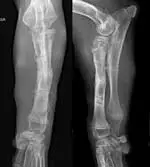

This procedure first required temporary proximal distraction of the humerus using a transarticular extension of the fixator to provide clearance for the radial head. Once the radial head was repositioned under the humeral condyle, the distraction of the humerus was discontinued and the transarticular component of the fixator removed (Figure 4). The fixator was maintained for 4 weeks until clinical union was achieved. At that point the fixator was removed.

Figure 4: Frontal plane radiograph of the antebrachium after reduction of the radial head and removal of the transarticular component of the circular external fixator frame

OutcomeAt a follow-up appointment 4 weeks after fixator removal, the puppy remained slightly lame in the left forelimb but showed subjective improvement from thepreoperative level of discomfort. The diminished range of motion remained unchanged. Still evident were antebrachial valgus and external torsion; it was noted that these issues may need to be surgically addressed in the future. Radiographs confirmed maintenance of reduction of the radial head but also showed remodeling and osteoarthritis (Figure 5).

Figure 5: Orthogonal radiographs of the affected antebrachium 4 weeks after removal of the external fixator. Note remodeling of the radial head despite the maintenance of its reduced positioning. Also noteworthy are the persistent angulation and torsion, which this technique does not address.